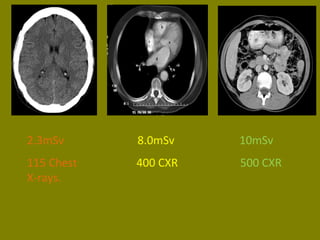

2.3mSv 8.0mSv 10mSv

115 Chest 400 CXR 500 CXR

X-rays.